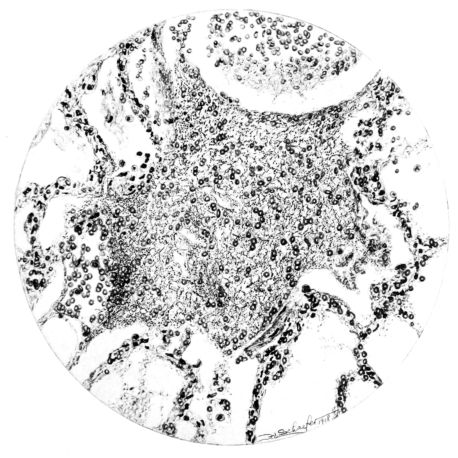

FIG. I. AUTOPSY NO. 99. ACUTE HEMORRHAGIC AND ULCERATIVE LARYNGOTRACHEITIS.

Early in the disease the congestion and the hemorrhages that have been described in the mucous membrane of the nasopharynx (14 and 94) are also conspicuous features in the lining of the trachea and bronchi (Fig. I). This membrane is swollen, turgid, red, and covered by a copious, mucous exudate which may be clear, but much more frequently is blood-stained or opaque and yellowish in color. The blood, variable in amount, may be fresh and red; and after the mucous exudate on the surface is removed, more intense red foci stand out on the congested base (47, 90, 157). Frequently, as the bronchi are approached, the red color of the mucosa becomes more intense and may have a garnet tinge. Membranes such as are encountered in the more usual necrotizing inflammatory processes, like diphtheria, have not occurred in the trachea and larger bronchi in this series (108, 128, 157).[3] The exudate peels off readily, and as indicated above, leaves a velvety red surface, 14dotted here and there with darker or more intensely red foci. Small ulcerations of the mucosa occur, but are inconspicuous (82, 156). As the finer ramifications of the bronchi are approached, the accumulation of the exudate in their lumina becomes more and more marked, and on cross section of the lung, they often stand out conspicuously on account of their increased size and projecting, seromucous, blood-stained content (101, 149, 162).